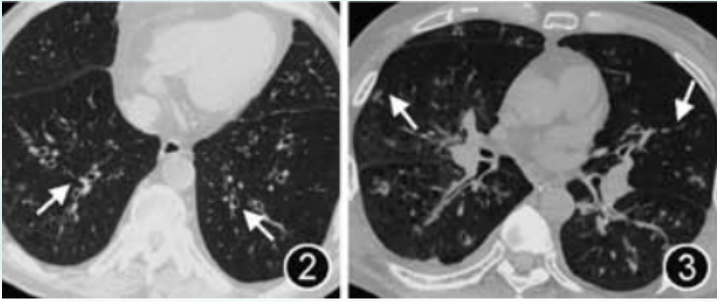

慢阻肺伴IPA的影像学表现为气管或支气管管壁增厚,伴有管腔狭窄支气管管壁增厚以大气道为著,通常为多叶段受累,偶见局限的叶段受累肺实质可以不受累,或仅有少量的磨玻璃或实性小叶核心结节。慢阻肺患者合并IPA在初始阶段大多为气道侵袭性。如果胸部CT表现为相对比较弥漫的支气管壁的增厚,伴有小叶核心结节和小叶中心型肺气肿改变,应警惕是否有沿气道侵袭的可能性(图1)并结合其他检查结果进一步诊断。

图片

1  气道侵袭性肺曲霉病支气管炎期患者胸部CT典型表现

图源:中华结核和呼吸杂志, 2024, 47(7):604-622.

与其他非粒细胞缺乏患者类似,慢阻肺患者合并IPA常缺乏典型的影像学表现,实变、结节、双侧渗出、树芽征等非典型影像学表现较为常见。2020年发表的一项针对123例慢阻肺合并肺曲霉病患者的回顾性研究显示,在影像学检查中,曲霉病典型的新月征和晕轮征在单纯慢阻肺基础疾病患者中少见(发生率为0~5%),空洞可见于疾病进展后期。因此,当慢阻肺患者出现与影像学表现不匹配的呼吸困难、喘息(尤其是当抗菌治疗失败或好转后再加重、糖皮质激素治疗难以缓解)时应警惕IPA的可能性。